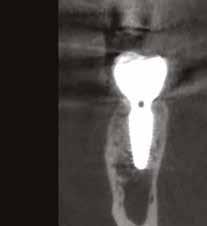

6. kép: Implantátum-ágy preparáció. 7. a–b. képek: Implantátum behelyezés. 8. kép: A behelyezett implantátum. 10. a–b képek: Azonnali ideiglenes korona készítése. 9. kép: Megfelelő primer stabilitás.

12. kép: A 6 hónapos intraorális kontrollröntgen felvétele.

A 2020 januárjában elkezdett kezeléssorozat befejezését az év márciusában, hazánkba is begyűrűző Covid-19 pandémia késleltette, így kb. 6 hónap gyógyulás után láttunk hozzá az emergencia profil és a gingivális zenit ideiglenes koronával történő formázásához (11. és 12. kép). A 3 hetente végzett apró alakításokkal sikerült megfelelő ínyprofilt kialakítani, a „rózsaszín esztétika” a páciens számára is megfelelő volt. A bal felső nagymetsző fog meziális kompozit tömés cseréjét követően, individualizált nyitott kanalas lenyomati fejet készítettünk: az akrilát ideiglenes korona profilját átlátszó szilikonnal lemásoltuk, majd a körszimmetrikus gyári lenyomati fej és az ideiglenes korona kontúrja közötti hézagot folyékony kompozittal töltöttük ki (13. kép). Az így készített egyéni lenyomati fejjel vettünk lenyomatot a végleges, kerámialeplezésű cirkónium-dioxid vázas, átmenő csavaros rögzítésű koronához. (A fogtechnikai munkát Nébl Péter fogtechnikusmester készítette.), (14., 15., 16 és 17. képek).

A kész korona átadásakor a páciens elégedett volt az esztétikával, az azóta eltelt évben rendszeres kontrollokon jelent meg, melyek során meggyőződtünk a kemény- és lágyszövetek stabilitásáról (18. és 19. képek).

17. a–b képek: A kész munka átadáskor. 18. a–c képek: 1 éves kontroll. 19. kép: Intraorális kontroll röntgen felvétele 1 évvel az átadás után.